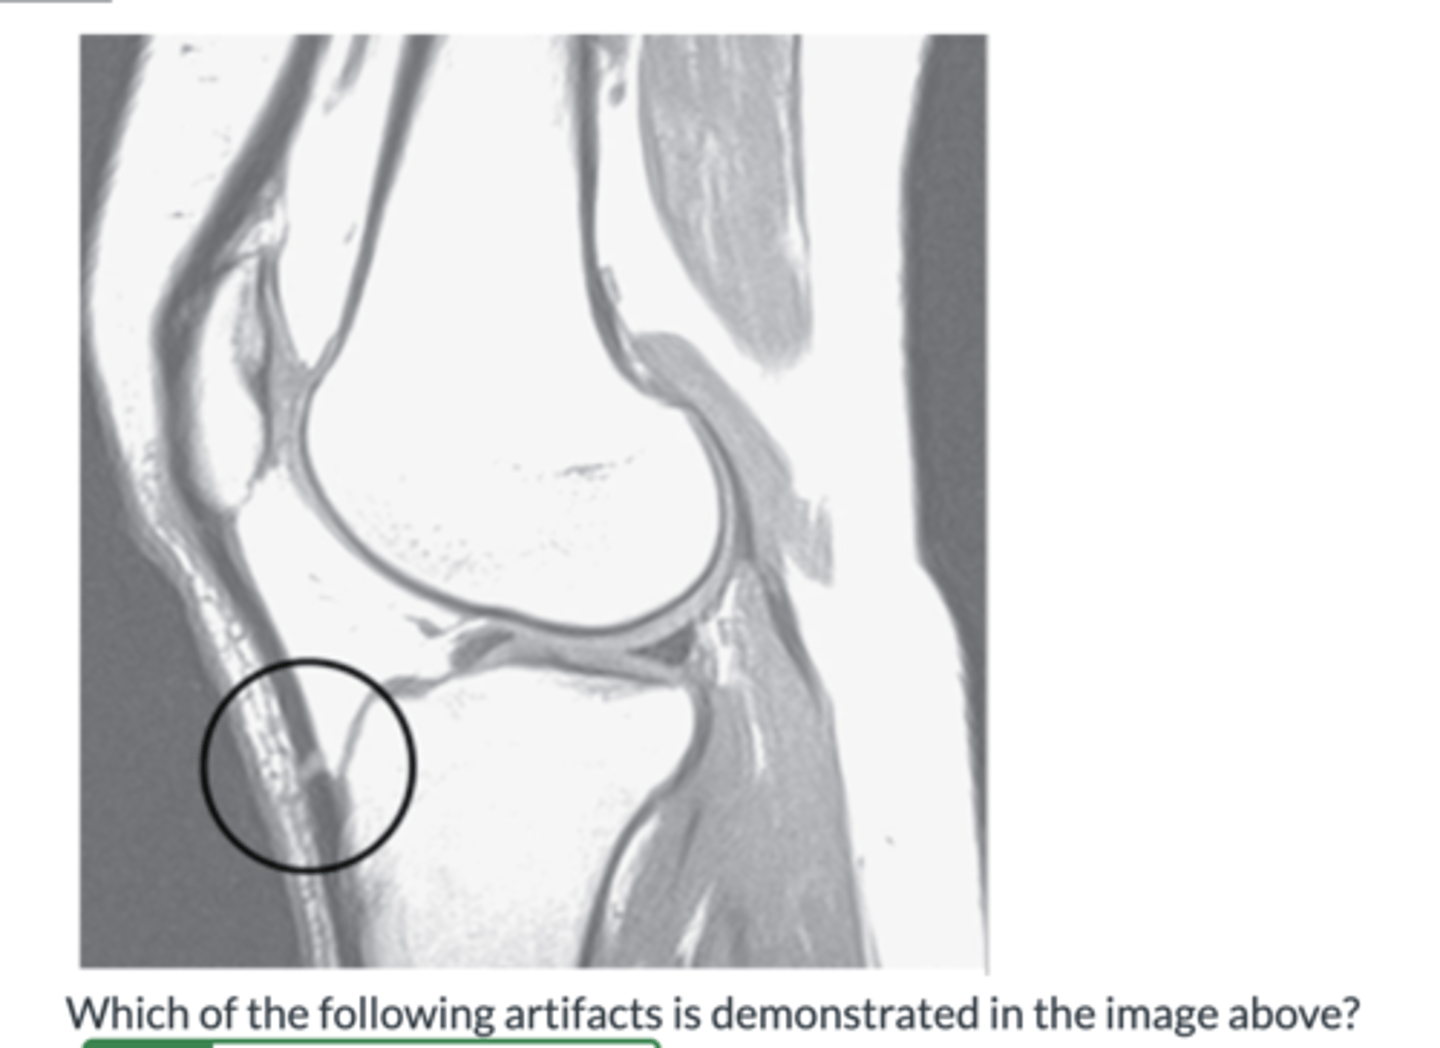

Magic Angle Artifact